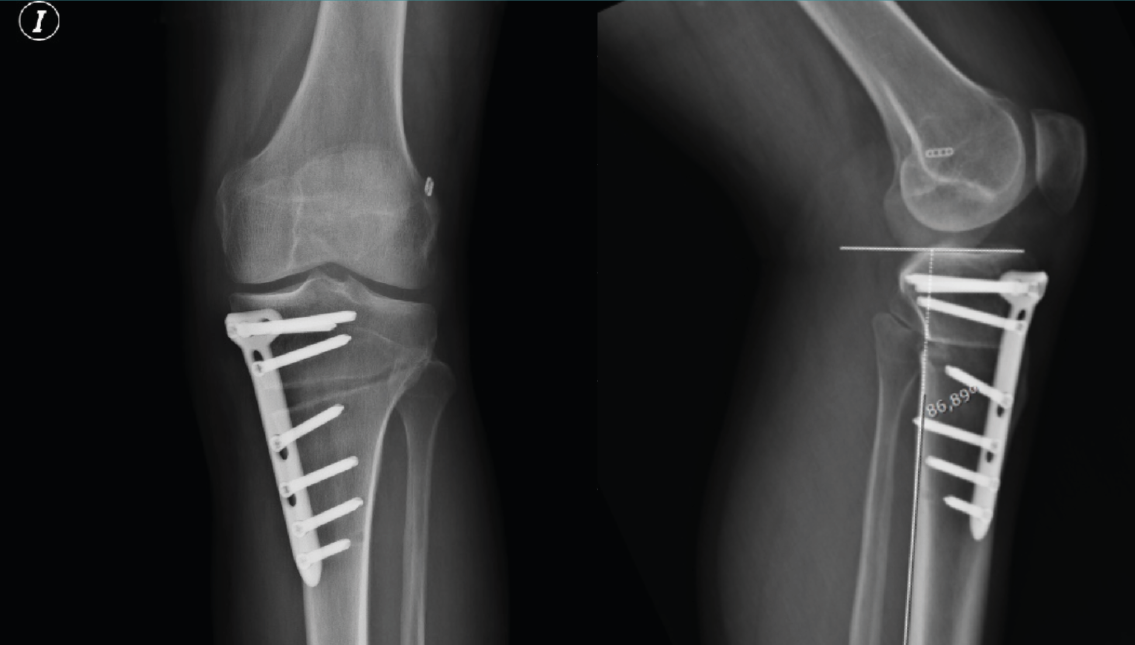

Figura 10. Radiografía de control a los 3 meses en proyecciones anteroposterior y lateral. En la proyección lateral se aprecia que no se modifica la pendiente tibial posterior tras la osteotomía tibial alta de apertura medial.